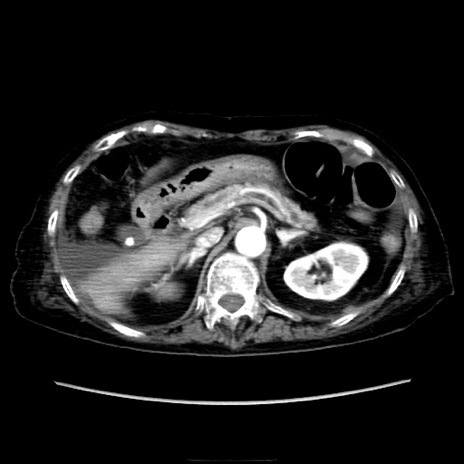

他院CT

横断像